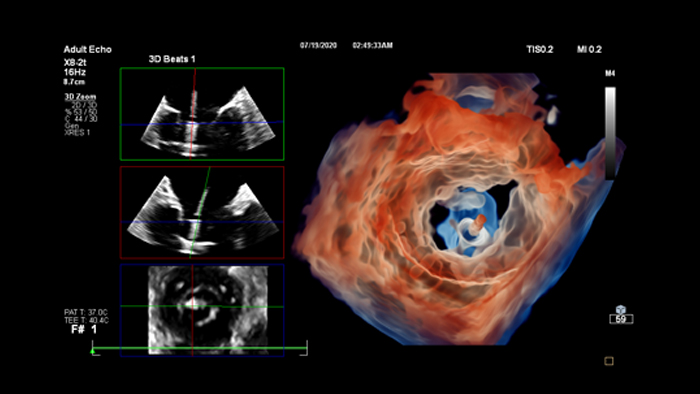

Wir zeigen, wie Bildgebungstechnologien durch ausgezeichnete Qualität bei der diagnostischen Bildgebung, mittels Analysen, Berichterstellung und durch Einblicke über verschiedene Bildgebungsmodalitäten hinweg lebensverändernde klinische Erkenntnisse für Patienten und kardiologische Behandlungsteams bieten. Dabei unterstützen sie gleichzeitig die Arbeitsabläufe, Effizienz und Zufriedenheit der Mitarbeiter.

Prüfen, analysieren und quantifizieren Sie klinische Daten von verschiedenen Modalitäten und für unterschiedliche klinische Indikationen mit KI-gestützten 3D-Modellen, Kartendarstellungen und anderen Quantifizierungsfunktionen.